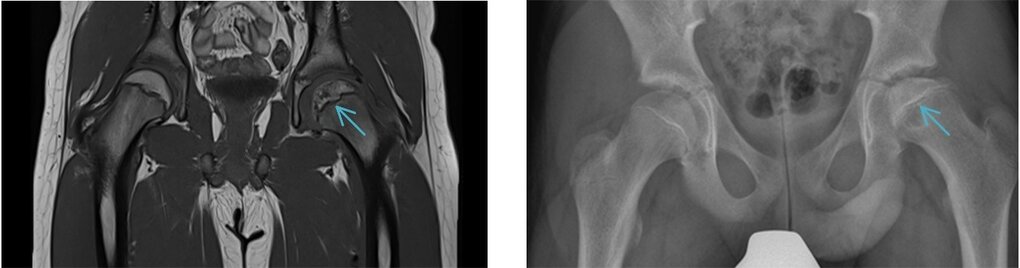

Durch eine verminderte Durchblutung kann es zu einem Absterben des Knochens im Hüftkopf kommen. Bricht dieses Knochenareal zusammen, kommt es zu einer Unregelmäßigkeit der darüber liegenden Gelenkfläche des Hüftkopfes. Aus der Inkongruenz zur Gelenkfläche des Beckens resultiert eine frühzeitige Arthrose.

Therapiemöglichkeiten:

- Frühes Stadium: Durch Mikrofrakturierung des geschädigten Knochenareals unterhalb des Knorpels migrieren Stammzellen sowie biochemische Botenstoffe (z.B. Wachstumsfaktoren) aus dem Blut in die Läsion, wordurch sich der Knochen regeneriert.

- Spätes Stadium: Implantation einer Hüftprothese

Abb. links: MRT-Bild eines Hüftgelenkes. Der gelbe Pfeil zeigt auf den Herd der Femurkopfnekrose.

Abb. rechts: Intraoperatives Röntgenbild. Der Herd wird angebohrt (mikrofrakturiert).